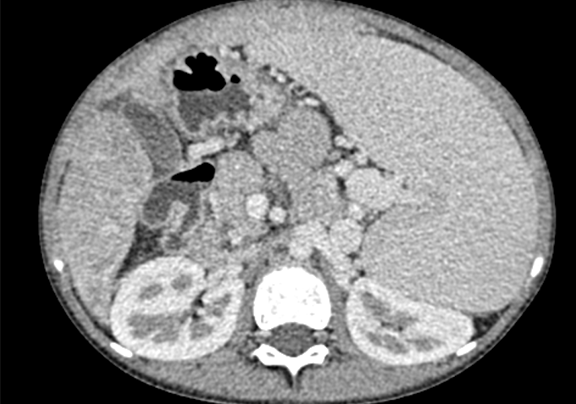

下腹部增强CT示:考虑肝硬化、脾大、门脉高压、侧枝循环形成、腹水可能性大。

术前CT检查:

动脉期

静脉期